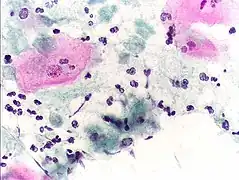

Classically, with a cervical smear, infected women may have a transparent "halo" around their superficial cell nucleus but more typically the organism itself is seen with a slight cyanophilic tinge, faint eccentric nuclei, and fine acidophilic granules.[30] It is unreliably detected by studying a genital discharge or with a cervical smear because of their low sensitivity. T. vaginalis is also routinely diagnosed via a wet mount, in which "corkscrew" motility is observed. Currently, the most common method of diagnosis is via overnight culture,[31][32] with a sensitivity range of 75–95%.[33] Newer methods, such as rapid antigen testing and transcription-mediated amplification, have even greater sensitivity, but are not in widespread use.[33] The presence of T. vaginalis can also be diagnosed by PCR, using primers specific for GENBANK/L23861.[34]

Pap smear, showing infection by Trichomonas vaginalis. Papanicolaou stain